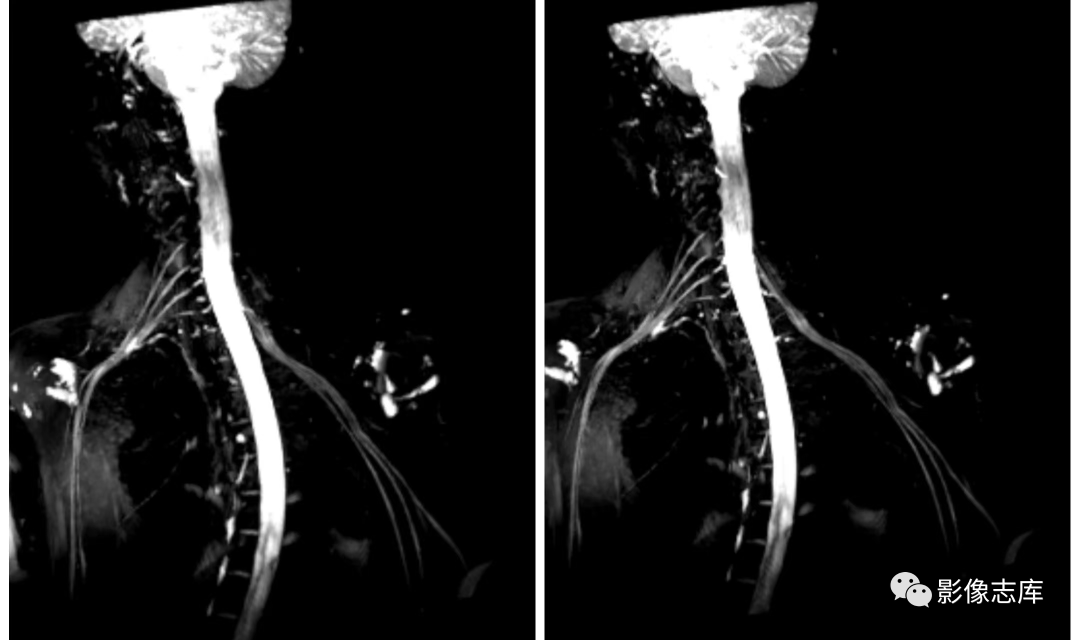

在臂丛神经扫描中,根据不同设备比如1.5和3.0T,我们选择的序列不同,总体原则就是跟扫描MRCP一样,凸显胆道系统,抑制背景组织,扫描臂丛神经也是一样的,凸显臂丛神经,抑制背景组织包括软组织、血管以及淋巴结等,因此也主要使用重T2加权成像,压脂主要选择STIR,但是有时候STIR压脂效果也不是太理想,因此还可以结合其他压脂技术,以西门子3.0T vida设备为例我们通常选择以下序列:

不打药和打药区别:利用重T2结合脂肪抑制STIR序列,可达到一定背景组织抑制的目的,但是血管和淋巴结很难将其抑制,为了达到这些组织不被显现,因此引入打药后的T2负性增强原理,由于微小血管和淋巴结可吸收少量对比剂,对比剂可缩短T2弛豫时间,因此通过打药后的T2加权可达到微小血管和淋巴结抑制的目的。

背景抑制:打药后进行T2 SPACE STIR cor 扫描,使背景抑制更彻底;

可实现各向同性:可进行3D等体素,扫描后可进行多方位重建,多角度观察臂丛神经;

高分辨:×450,明显提高图像空间分辨率;